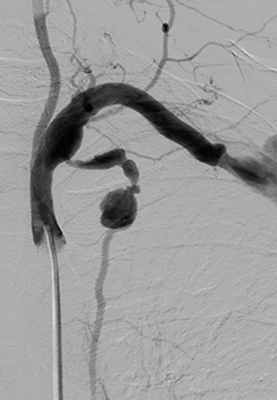

МСКТ аорты и артерий нижних конечностей: аневризма правой ОПА диаметром 38 мм на протяжении 76 мм, правой общей бедренной артерии (ОБА) диаметром 26 мм, протяженностью 58 мм с наличием пристеного тромбоза, а также тромбированной аневризмы подколенных артерий. Слева концентрическая пристеночно тромбированная аневризма дистального отдела поверхностной бедренной артерии, подколенной артерии диаметром 36 мм, длиной 40 мм. Диаметр аневризмы правой подколенной артерии 47 мм на протяжении 50 мм (рис. 1). Рисунок 1. Мультиспиральные компьютерные томограммы аорты и артерий нижних конечностей. Аневризма правых ОПА и ОБА. а - фронтальный срез. Рисунок 1. Мультиспиральные компьютерные томограммы аорты и артерий нижних конечностей. Аневризма правых ОПА и ОБА. б - сагиттальный срез.

ДС артерий нижних конечностей от 19.04.12: справа аневризма ОПА (диаметр 34,6 мм), аневризма ОБА (22,4 мм). Протезированная подколенная артерия, шунт проходим, в дистальных отделах голени кровоток магистрального типа.